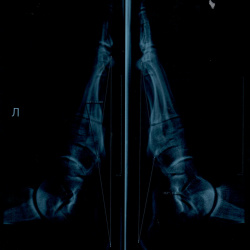

Пациент 21 год на призывной комиссии со снимком стоп в 2-х проекциях с функциональной нагрузкой.

С 2017 г. на занятиях физической культурой занимается в специальной подготовительной группе в...